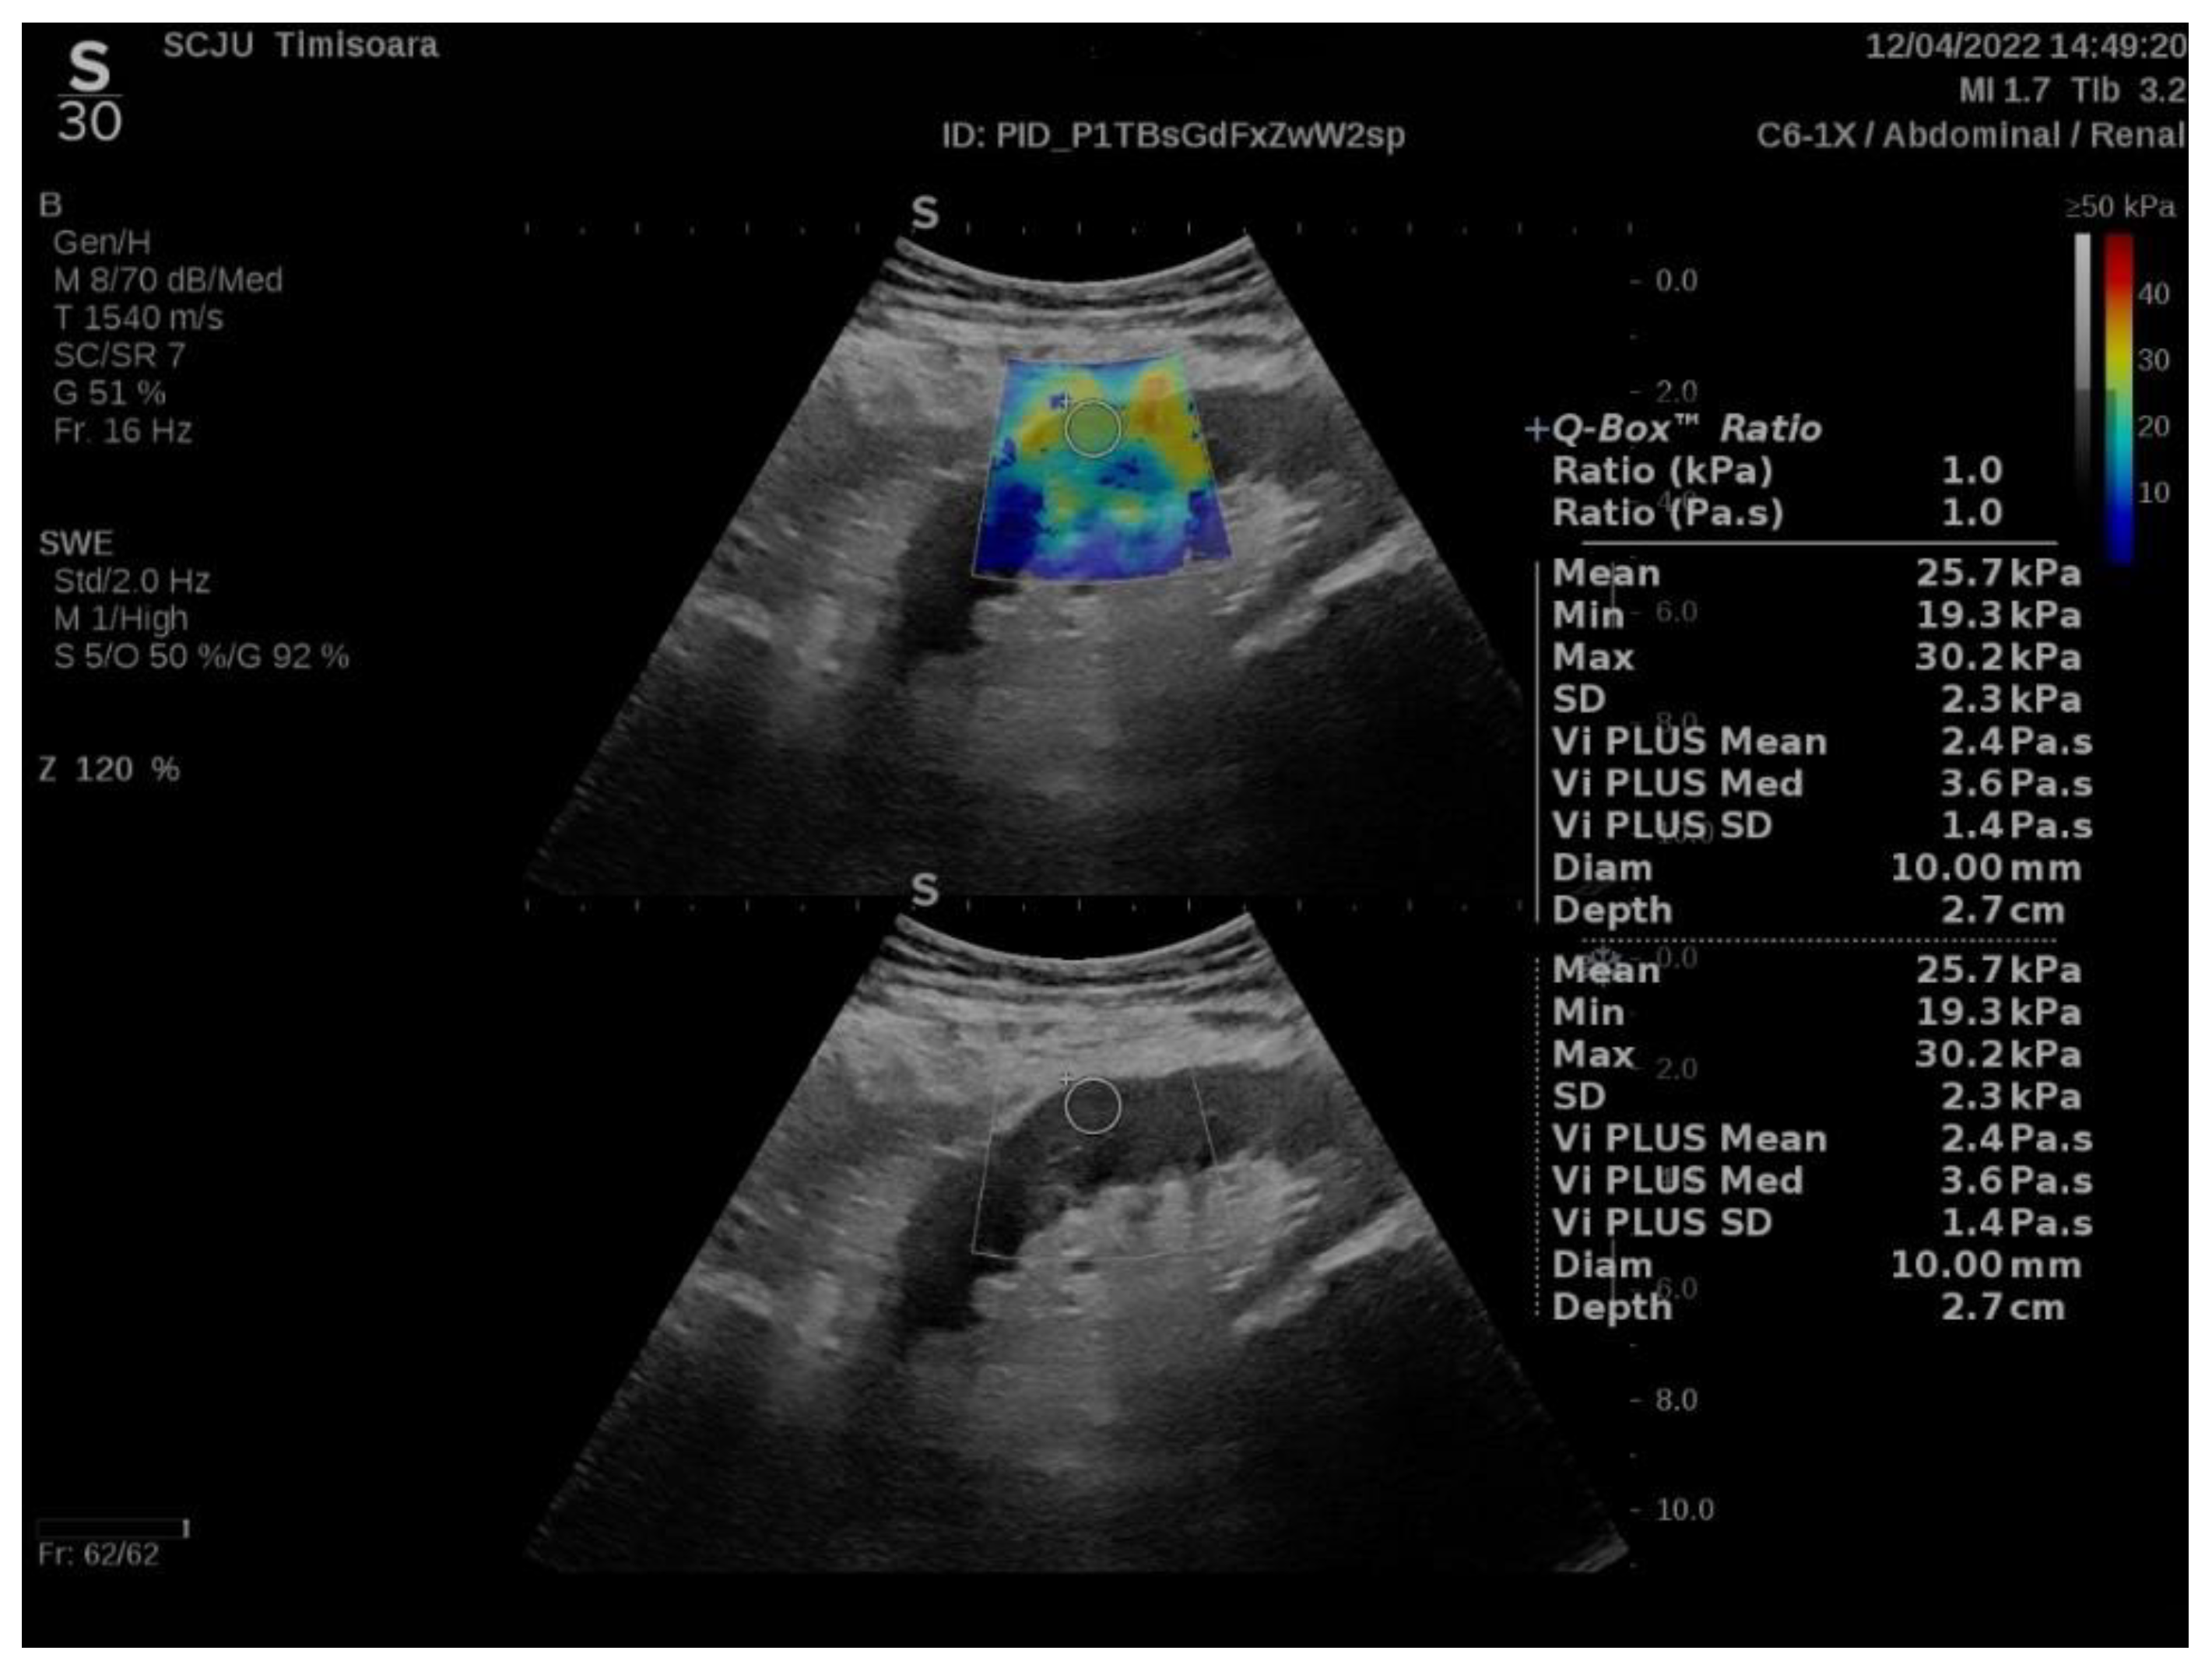

2.2. ShearWave PLUS Elastography

3. Results